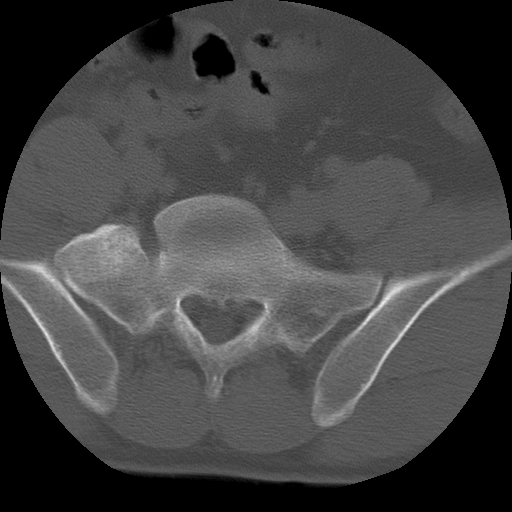

标题: CT24390:男,23岁,腰痛就诊。

男,23岁,腰痛就诊。

腰5右侧横突肥大伴假关节形成.

支持!图像少,再往下扫骶髂关节面,椎小关节毛糙,青年男性需排除as,实验室查b27。

腰5右侧横突肥大伴假关节形成

腰5右侧横突肥大伴假关节形成!支持!

l5右侧横突肥大伴假关节形成。

腰椎骶化或骶椎腰化常见。